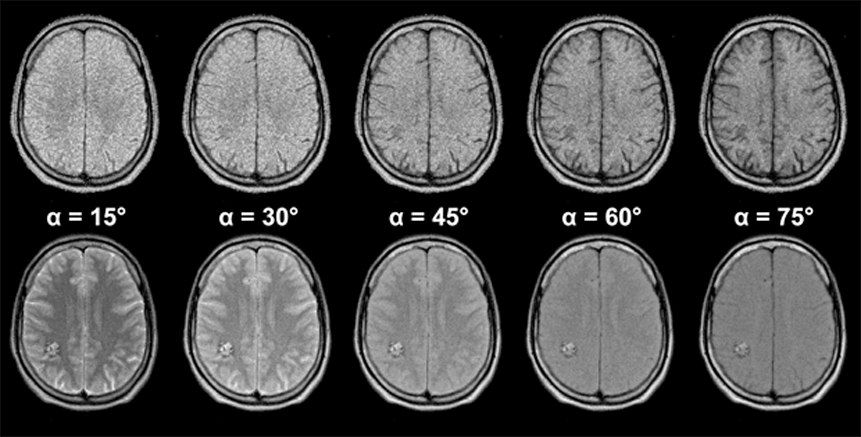

Figura 10-13:

Gradient echo pulse sequence (spoiled GRE) through the brain of a patient with a vascular mal­for­ma­tion in the right occipital hemisphere.

The upper image series was ta­ken with an echo time TE = 20 ms, the lower series with an echo time TE = 120 ms (B₀ = 1.5 T). The lesion is nearly invisible in the image series with short TE, but well de­li­ne­at­ed in the series with long TE.

The choice of the appropriate pulse se­quen­ce parameters is pivotal in MR ima­ging. Many different sequences can be applied for different diagnostic questions. In many instances, their contrast behavior has been recorded empirically and the se­quen­ce and specific sequence pa­ra­me­ters have been included in special clinical ima­ging protocols.

Simulation software: MR Image Expert®

As we have seen in the SE se­quen­ces, one can hide and miss pathological chan­ges by choosing the wrong pulse se­quen­ce. This also holds for rapid se­quen­ces. If we se­lect a T1-weighted se­que­nce, we cannot distinguish a lesion which possesses a si­mi­lar T1 to its neighboring tissues. If we apply a T2*-weighted sequence, we cannot de­li­ne­ate a lesion with a T2 close to the T2 of its surroundings. The signal intensity of the vascular malformation in Figure 10-13 is a good example of this problem.